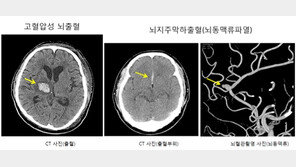

매일 500cc 맥주 2캔이나 소주 6~7잔을 마시는 사람은 그렇지 않은 사람보다 뇌출혈(뇌내출혈)이 평균 10년 이상 빠르게 발생하며, 출혈량이 더 많고 손상 정도도 훨씬 심각한 것으로 나타났다.미국 하버드대학교 의과대학과 협력관계인 대규모 비영리 의료·연구 네트워크인 매스 브리검 …